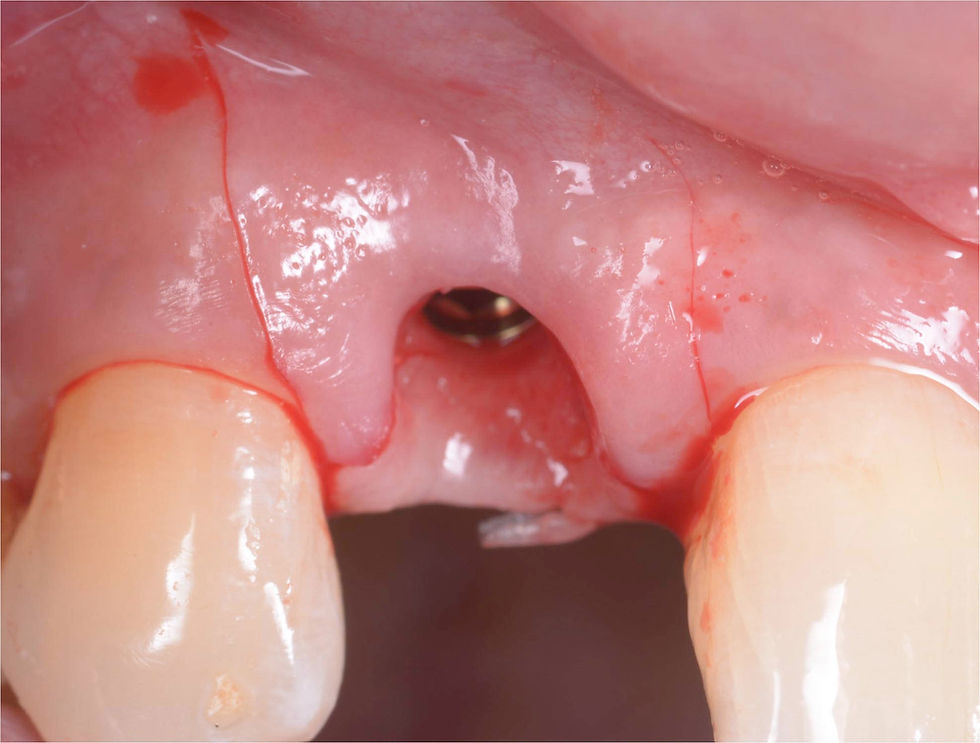

Removal of the temporary crown after 4 weeks. The epithelialized tissue around the edges of the crown is still maturing but the adaptation on the morphology of the crown is already visible.

Images 30 days after surgery: modulation of the temporary crown for the progressive adaptation of soft tissues. The crown is reduced by about 3 mm.

After 1 month, the mucosal tissue is adjusted on the new profile both mesially and distally and has almost reached the prefixed purpose.